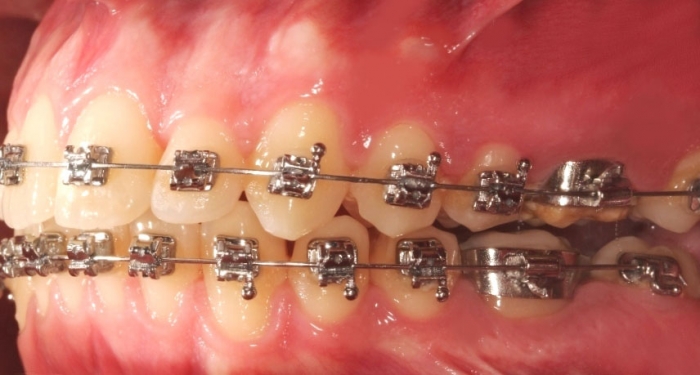

Mordida inicial - Clínica Cliniface

Mordida inicial